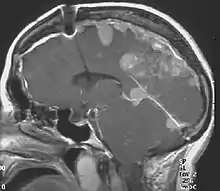

Neurofibromatosis type II (also known as MISME syndrome – multiple inherited schwannomas, meningiomas, and ependymomas) is a genetic condition that may be inherited or may arise spontaneously. The main manifestation of the condition is the development of bilateral benign brain tumors in the nerve sheath of the cranial nerve VIII, which is the "auditory-vestibular nerve" that transmits sensory information from the inner ear to the brain. Besides, other benign brain and spinal tumors occur. Symptoms depend on the presence, localisation and growth of the tumor(s). Many people with this condition also experience vision problems. Neurofibromatosis type II (NF2 or NF II) is caused by mutations of the "Merlin" gene,[2] which seems to influence the form and movement of cells. The principal treatments consist of neurosurgical removal of the tumors and surgical treatment of the eye lesions. Historically the underlying disorder has not had any therapy due to the cell function caused by the genetic mutation.

The so-called acoustic neuroma of NF2 is in fact a schwannoma of the nervus vestibularis, or vestibular schwannoma. The misnomer of acoustic neuroma is still often used. The vestibular schwannomas grow slowly at the inner entrance of the internal auditory meatus (meatus acousticus internus). They derive from the nerve sheaths of the upper part of the nervus vestibularis in the region between the central and peripheral myelin (Obersteiner-Redlich-Zone) within the area of the porus acousticus, 1 cm from the brainstem.